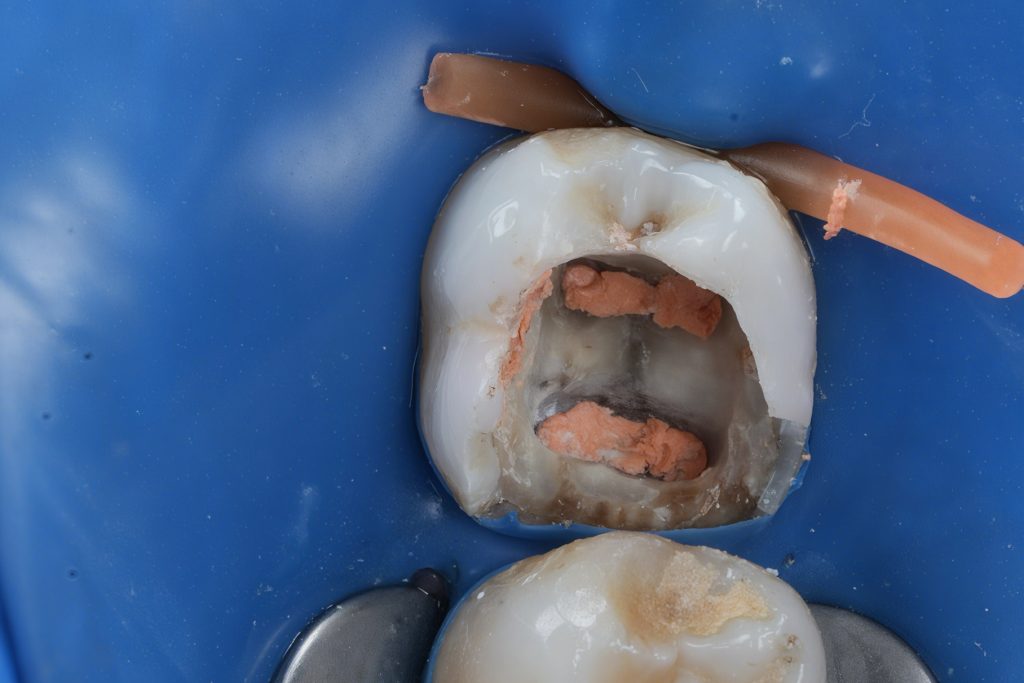

6️⃣ Class II Proximal Reinforcement

The proximal defect was restored immediately post-obturation.

- Garrison sectional matrix system used for tight proximal contact and contour (Fig 6).

- GC EverX Flow placed as the first 1–2 mm layer to reinforce weakened dentin.

- Incremental build-up completed with Tokuyama Estelite Sigma Quick (A2).

- Fig 6: Class II build-up using Garrison matrix + GC EverX Flow.